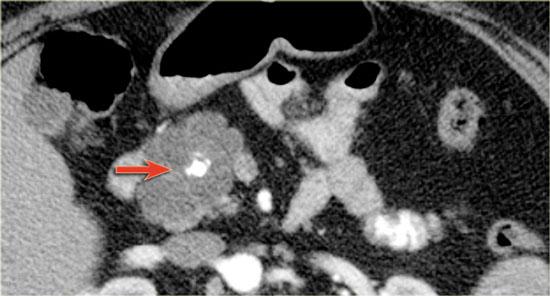

Hình ảnh CT của một IPMN với ống tụy giãn (mũi tên xanh).

Lưu ý nốt đặc có ngấm thuốc tại đầu tụy (mũi tên đỏ).

Tiếp tục xem hình ảnh siêu âm.